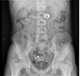

Pill ingestion